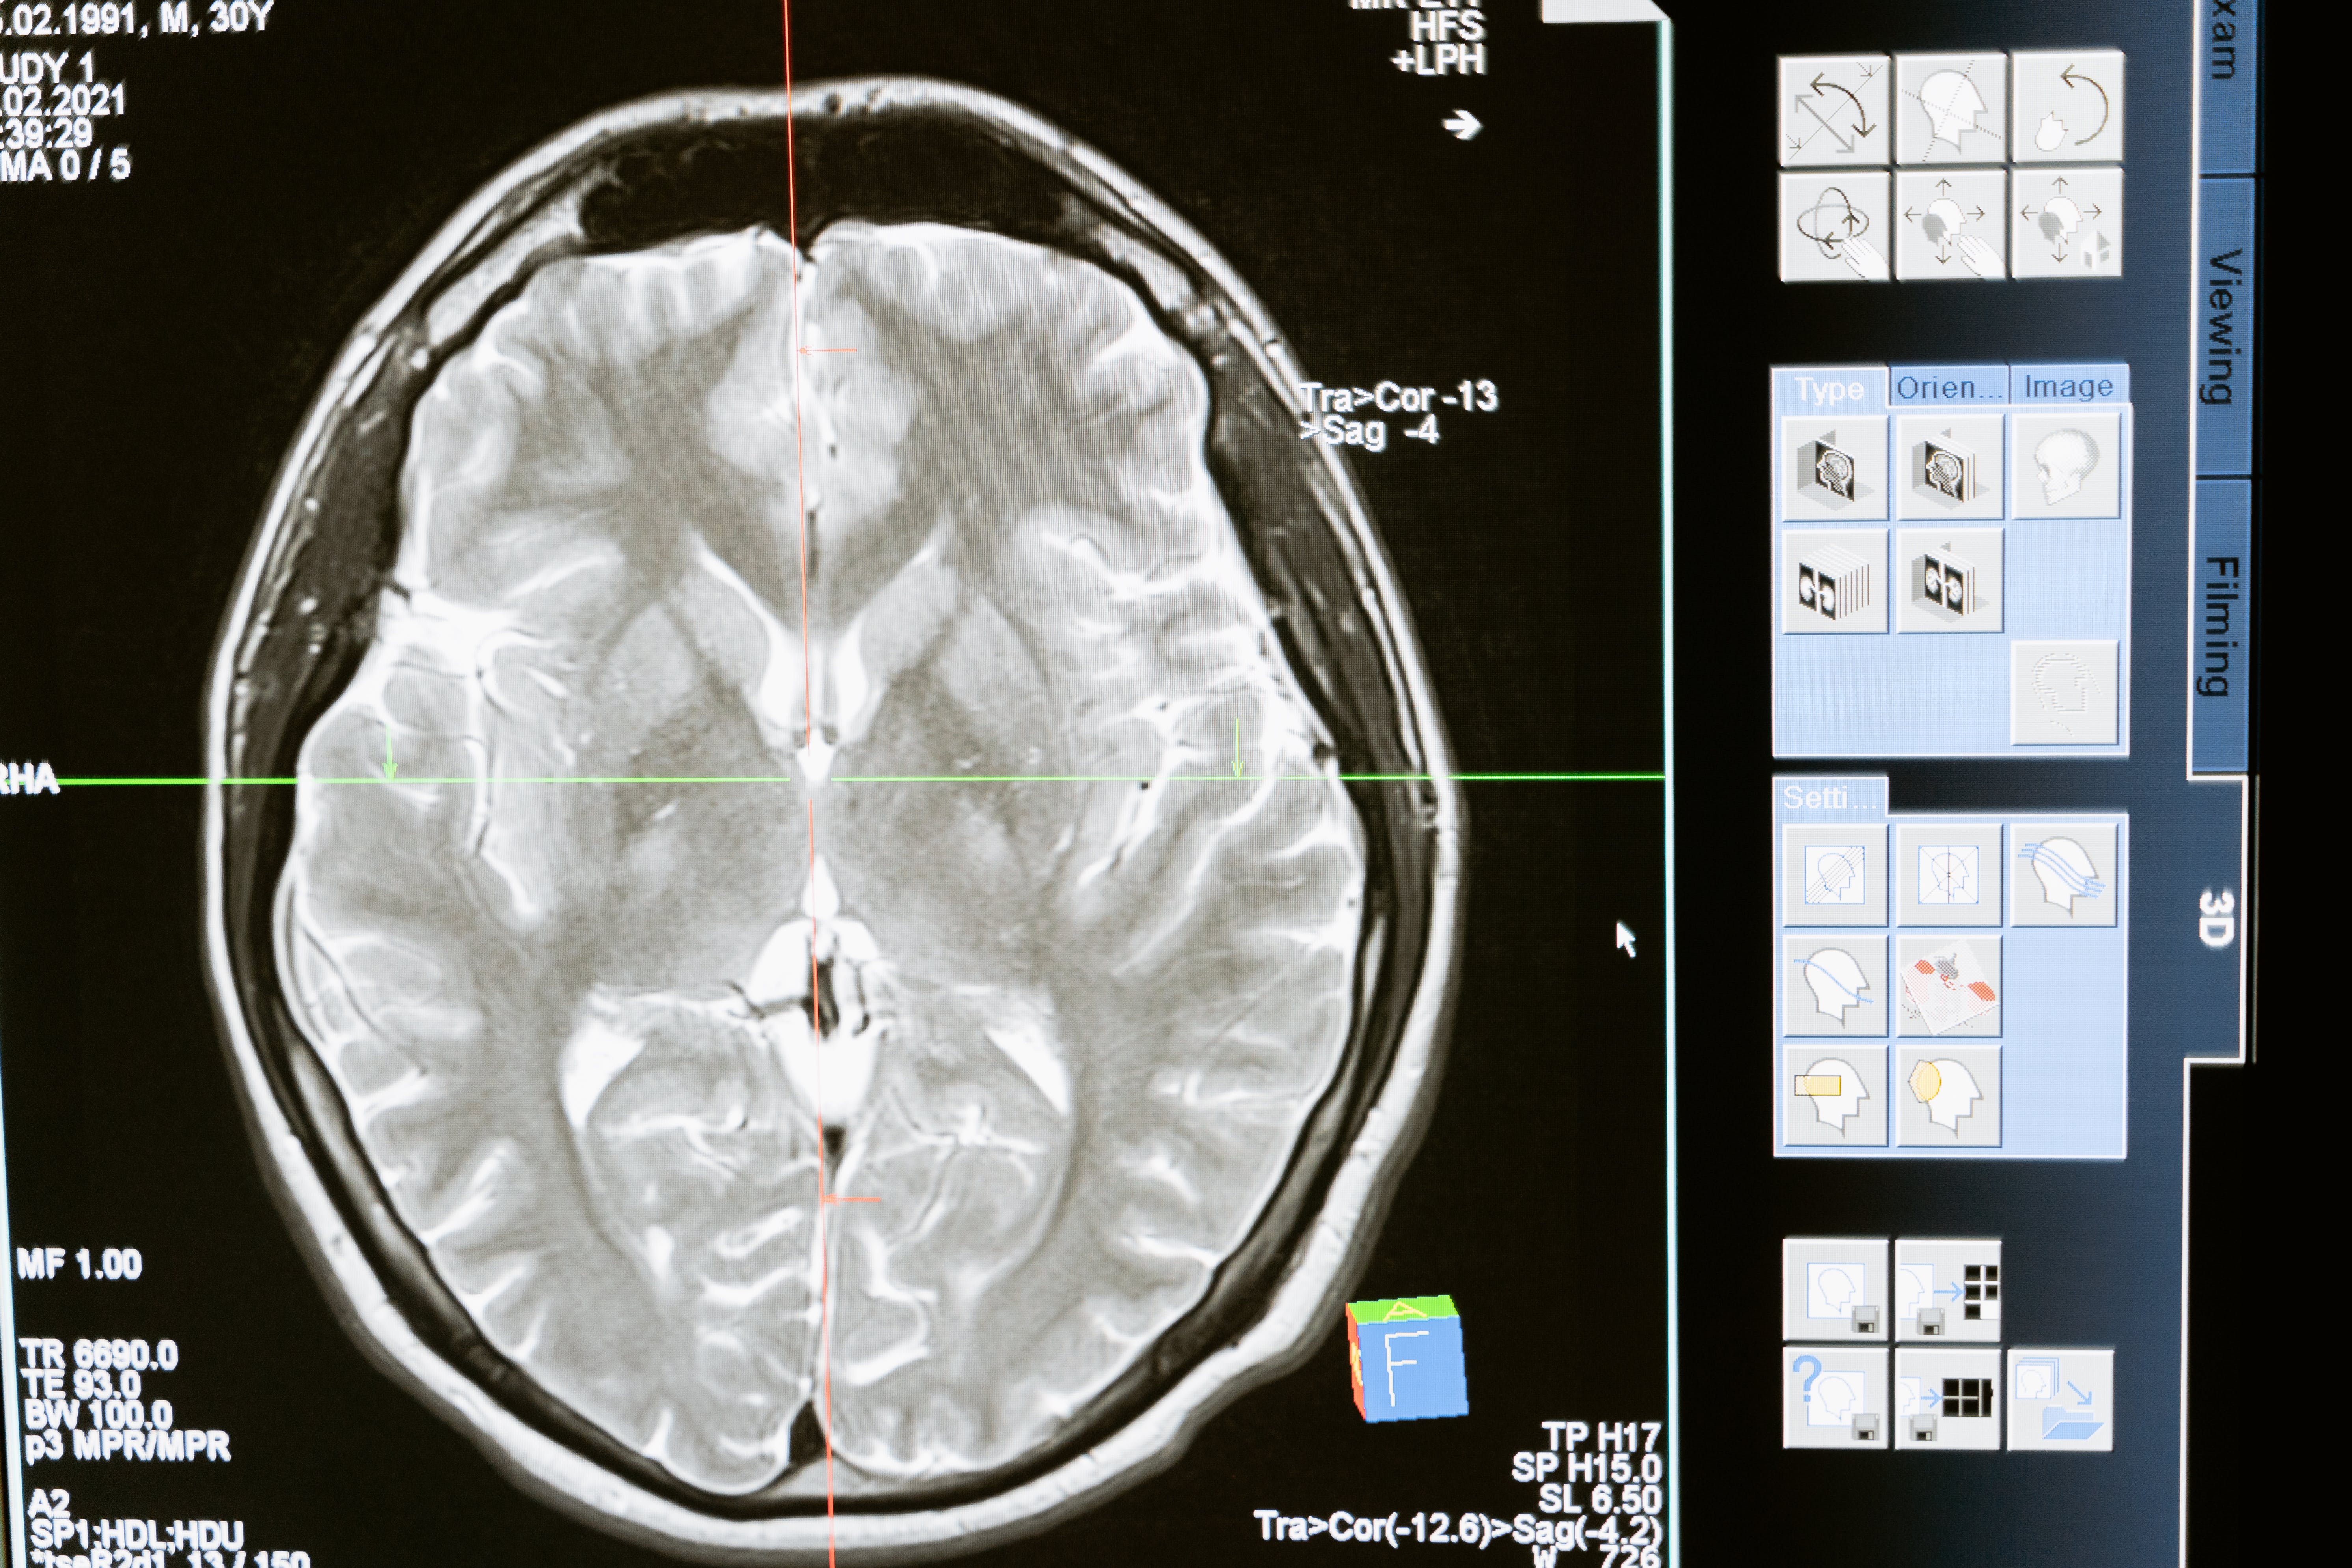

Brain research requires the analysis of massively detailed data sets generated by increasingly powerful techniques to measure brain structure and function such as MRI, MEG and EEG.